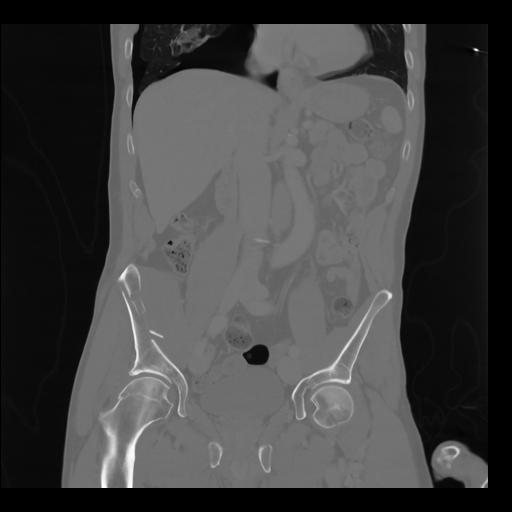

35 CUERPO,CE,Coronal,3.000,CUERPO,Coronal,